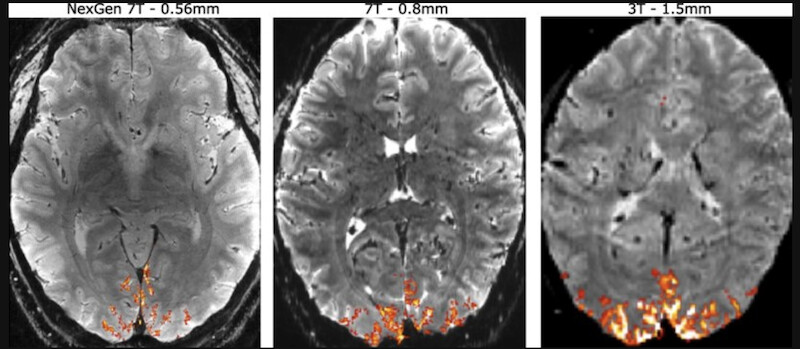

Le terme "Tesla" (nommé d'après l'inventeur Nikola Tesla) est l'unité qui mesure la puissance d'un champ magnétique. Pour vous donner une idée, une IRM standard dans un hôpital fonctionne généralement à 1,5 ou 3 teslas. Une machine à 7 teslas est donc plus de deux fois plus puissante que les meilleures IRM classiques.

Alors qu'une IRM classique peut voir des détails de la taille d'un grain de riz, l'IRM 7T descend à la taille d'un grain de sable (environ 400 microns). Cette précision permet aux chercheurs de voir non seulement les grandes zones du cerveau, mais aussi les différentes couches du cortex (l'écorce du cerveau) et les petits amas de neurones.

Dans le cadre de l'article sur l'alcoolisme, l'IRM 7T a permis de voir :

- La neuroinflammation en direct : On peut observer la réaction des petites cellules de défense du cerveau (la microglie) qui s'activent après une cuite.

- Les micro-lésions : Elle détecte des dommages minuscules dans l'hippocampe que les machines classiques ne voyaient pas, expliquant pourquoi certains jeunes ont des pertes de mémoire même si leur IRM à l'hôpital semblait "normale".